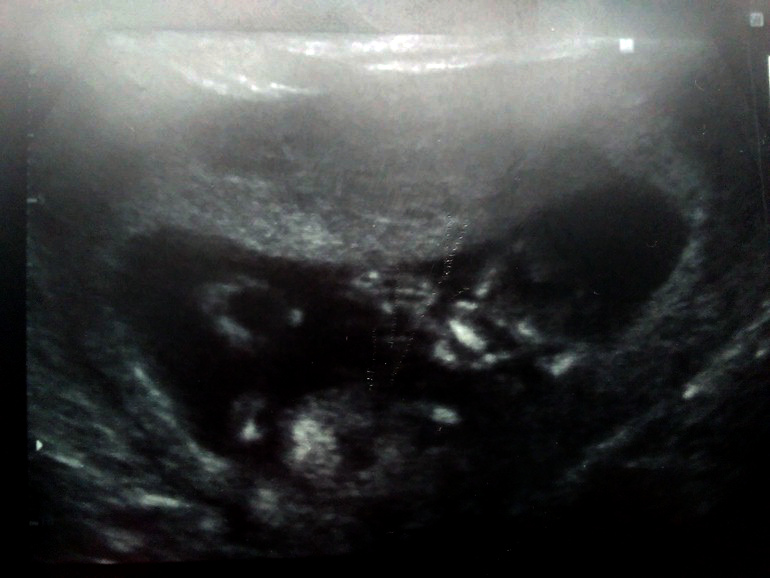

КТР 72мм,что соответствует 13.3 нед. беременности.

ЧСС 157 уд.в мин.

ТВП 1.7 мм.

ДКН 2.8 мм

И вобщем-то по узи все супер,кроме тонуса.Малыш такой активный,такой клевый .Ручкой помахал маме,пальчик пососал,ножки то вытягивал,то обратно.Пинался как мог бедный,от того что весь зажат,мой малыш

Фото прилагаю .как мы пальчик сосем